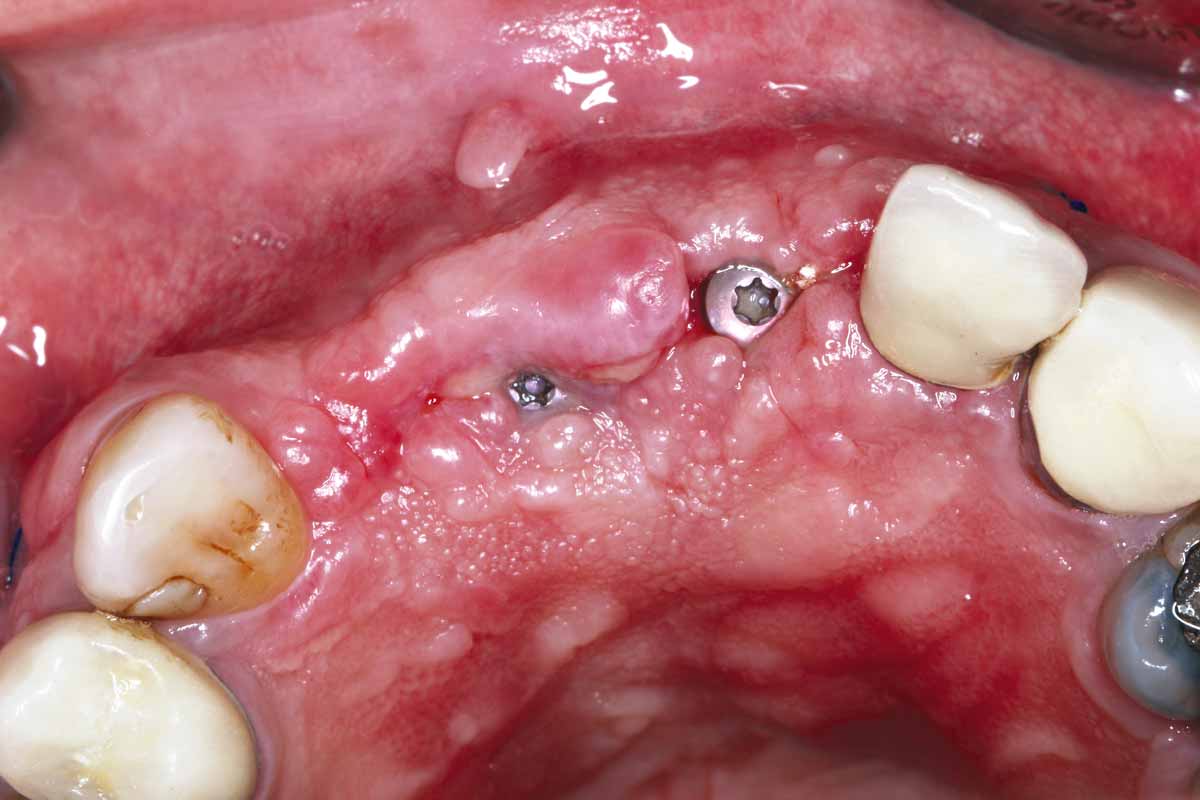

7/27 - Implants with healing caps

GBR and soft tissue augmentation with cerabone® and mucoderm® - H. Maghaireh & V. Ivancheva